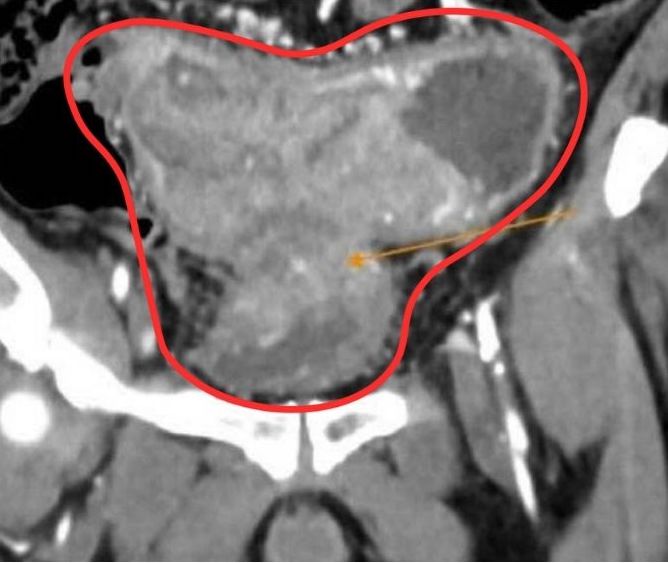

Gia đình đưa ông M. trở lại Bệnh viện đa khoa Tâm Anh TP.HCM khám. Kết quả chụp CT bụng ghi nhận khối u ác tính gây hẹp hoàn toàn lòng ruột gây giãn ứ phân, xâm lấn gây dày thành bàng quang. Đặc biệt gan có hai tổn thương do u đại tràng di căn đến.

Khối u ác tính gây hẹp hoàn toàn lòng ruột gây giãn ứ phân, xâm lấn gây dày thành bàng quang